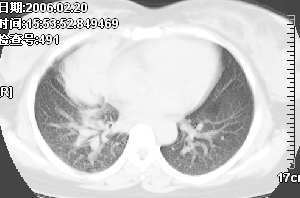

女,28岁咳嗽无痰偶有低烧,化验:白细胞1万零7,血沉正常

右肺上叶前段与中叶见较大团块影。边界较清晰,纵隔隆突前淋巴结增大。考虑1肺部间叶组织肿瘤可能。2感染性病变

我觉得不要把患者年龄作为轻易排除肺癌的依据,病变呈大块状软组织密度,右肺中叶支气管可见中断,右侧肺门增大,要高度警惕肺癌,支气管镜应该能够给出正确的诊断。间质来源的恶性肿瘤尽管可以考虑到,但是从发病率上来说不首先考虑。

已经手术结果为淋巴瘤

补充病例结果是:肺间变大t细胞淋巴瘤. 非霍奇金淋巴瘤(间变大t细胞性)iv期bipi 2分

右肺中下叶切除